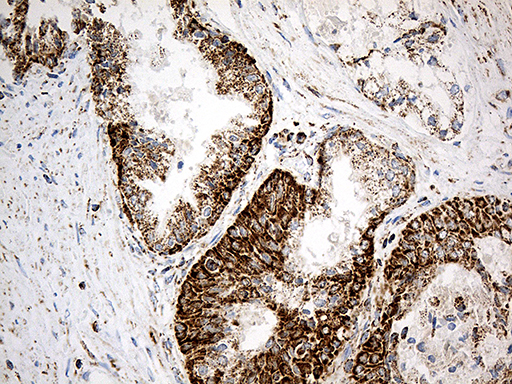

• IHC analysis of 14-3-3 Epsilon/YWHAE using anti-14-3-3 Epsilon/YWHAE antibody (M01687-2).

14-3-3 Epsilon/YWHAE was detected in a paraffin-embedded section of human Colorectal adenocarcinoma tissue. Biotinylated goat anti-mouse IgG was used as secondary antibody. The tissue section was incubated with mouse anti-14-3-3 Epsilon/YWHAE Antibody (M01687-2) at a dilution of 1:200 and developed using Strepavidin-Biotin-Complex (SABC) (Catalog # SA1021) with DAB (Catalog # AR1027) as the chromogen.